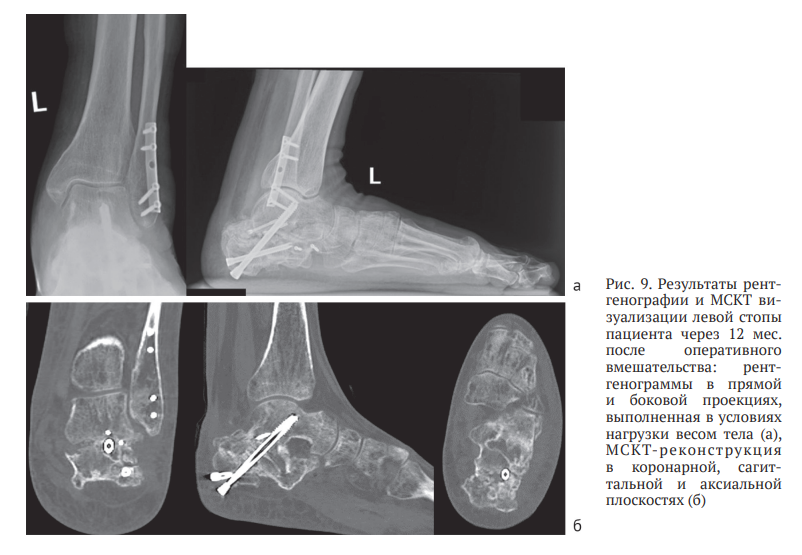

В течение месяца осевая нагрузка на конечность была полностью восстановлена, что позволило пациенту вернуться к трудовой деятельности. Динамическое наблюдение за пациентом продолжали, окончательный результат лечения оценен через 12 месяцев после операции. На контрольном осмотре отмечено сохранение достигнутой коррекции заднего отдела левой стопы, отсутствие латерального пяточно-малоберцового импиджмента, восстановление угла отклонения таранной кости, угла наклона пяточной кости, угла Мири, лодыжечного роста и ширины пяточной кости (рис. 9, а). Результаты МСКТ демонстрировали консолидированный артифициальный перелом левой пяточной кости с формированием подтаранного костного блока в условиях фиксации винтами, а также консолидированный перелом малоберцовой кости в условиях фиксации блокируемой пластиной (рис. 9, б).

Для визуальной оценки результатов хирургического лечения выполнена трехмерная реконструкция левой стопы на основе данных МСКТ, проведенной через 12 месяцев после оперативного вмешательства. На основании этих данных методом аддитивного производства (3D-печати) изготовлена пластиковая модель стопы, которую сравнили с исходной пластиковой моделью, напечатанной до проведения хирургического лечения на этапе предоперационного планирования (рис. 10). Наблюдали коррекцию латерального пяточно-малоберцового импиджмента и устранение вальгусной деформации заднего отдела стопы. Фотографии моделей левой стопы демонстрируют увеличение «лодыжечного роста» на 10 мм по сравнению с предоперационной моделью (рис. 10, б).